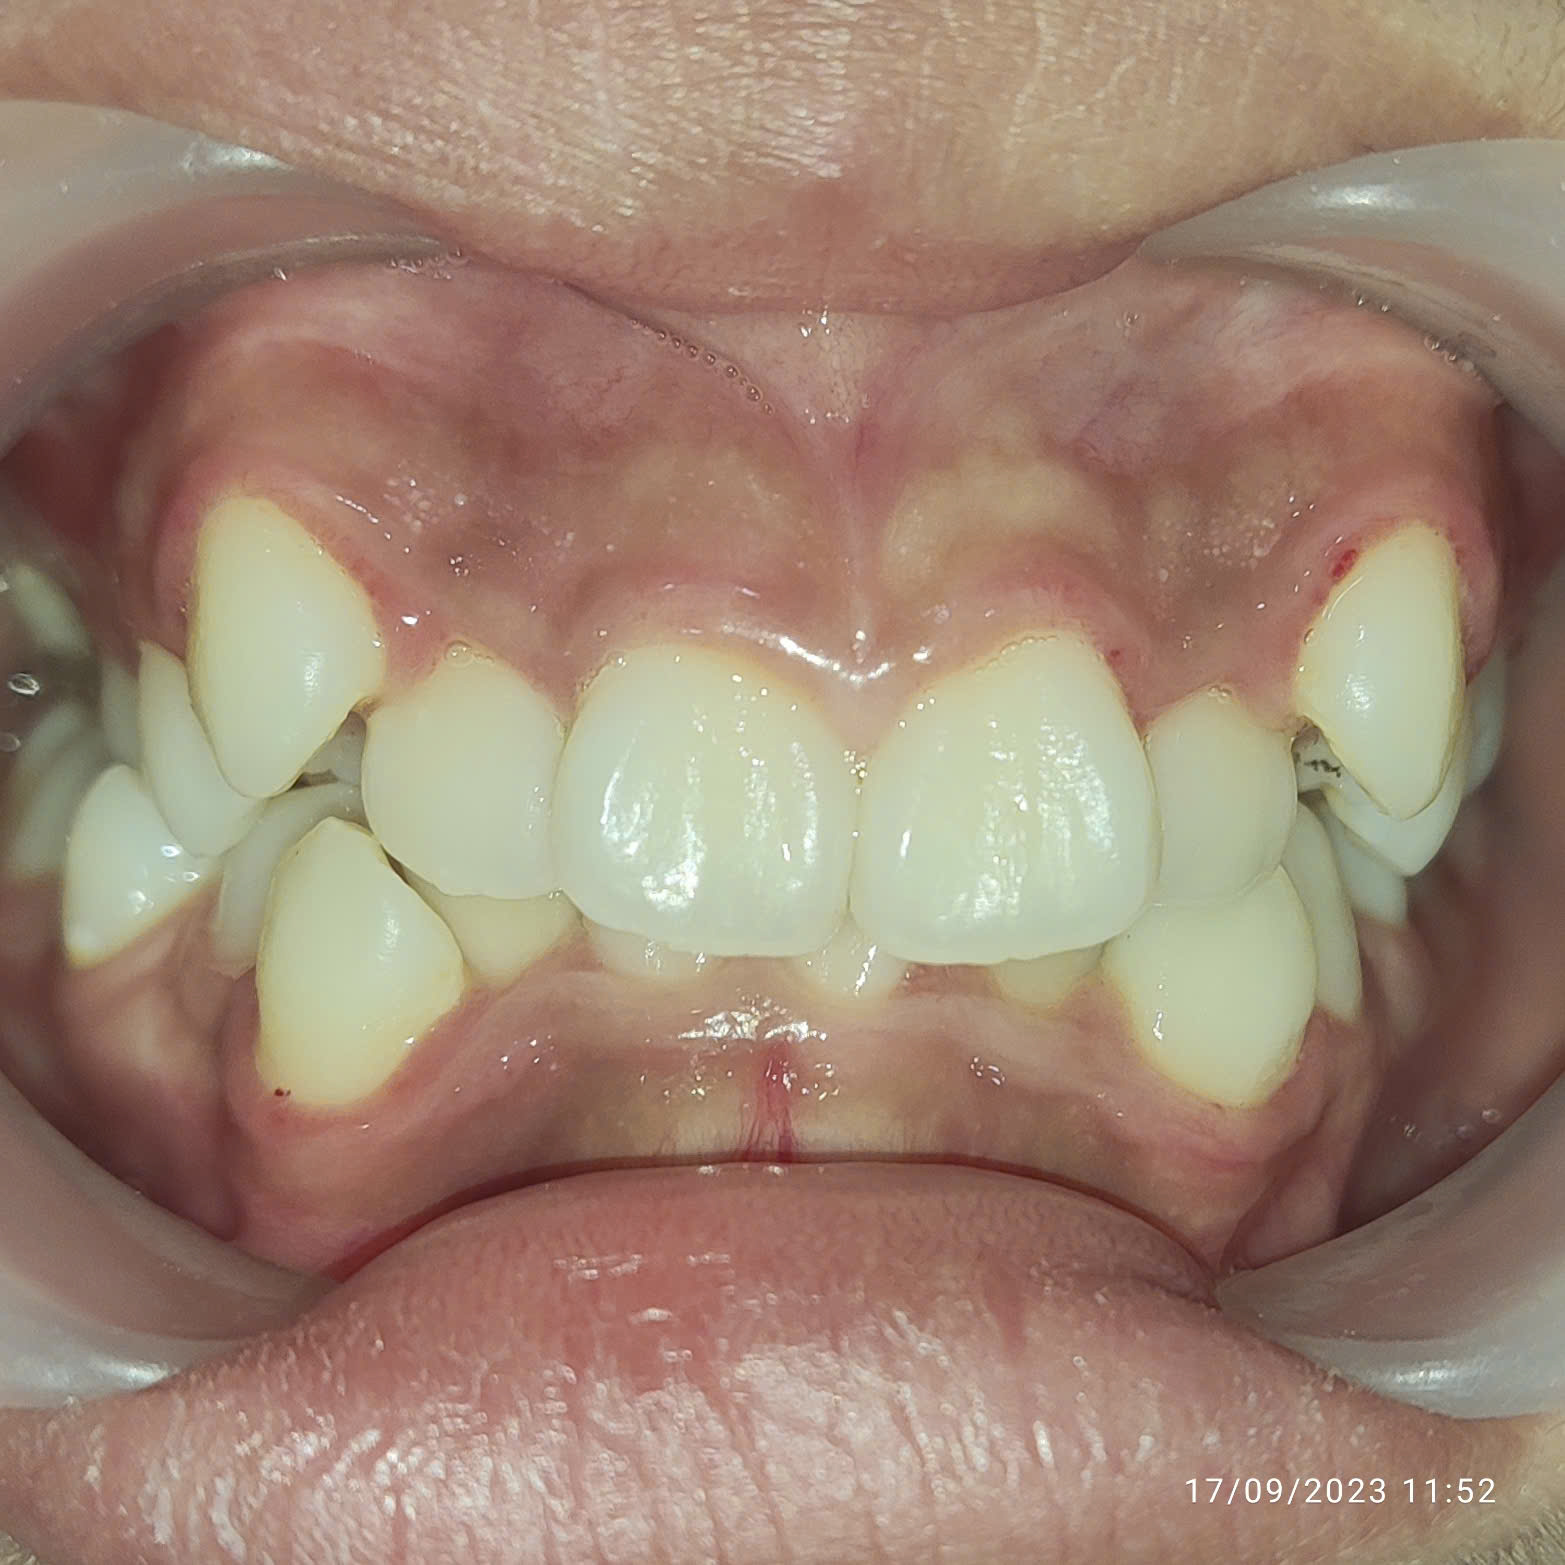

Khách hàng sau điều trị

Thấy con tự ti vì răng khấp khểnh, ba mẹ của Khánh Linh đã đưa bạn đến thăm khám và lựa chọn niềng răng tại Nha khoa Việt Mỹ.. Nhờ can thiệp kịp thời ngay ở độ tuổi vàng, chỉ sau hơn 1 năm, tình trạng răng của Khánh Linh đã được cải thiện rõ rệt khi răng dần dịch chuyển đúng vị trí, gương mặt của con cũng hài hòa hơn.